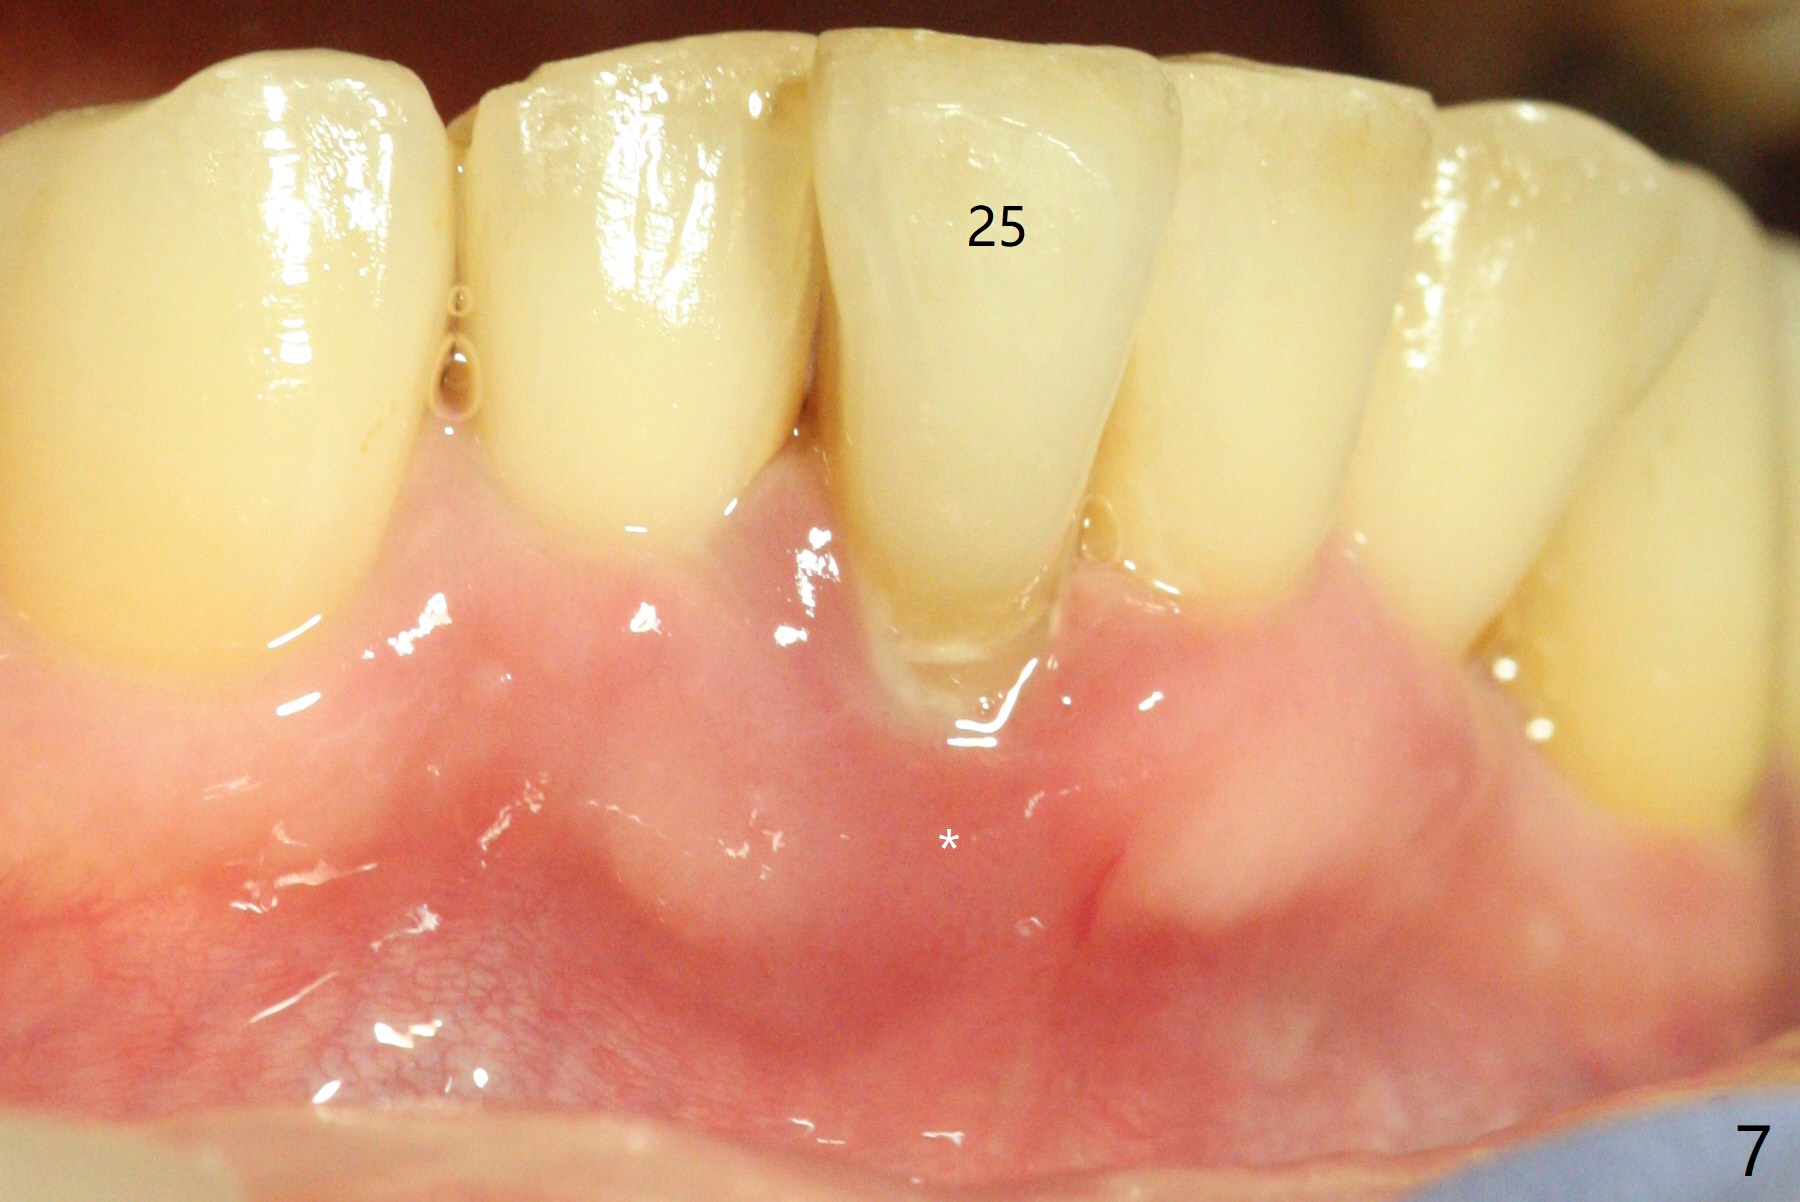

A 47-year-old man, a possible bruxer (Fig.1), is concerned about the mobile 2nd molar and lower central incisor (Fig.2,3). To prevent periimplantitis, a 2 mm 1-piece implant and a short one (5x5 mm) will be placed subcrestal at these sites, respectively (Fig.4,5). Sticky bone is a must. Pulpal test will determine whether RCT is required for #30 (Fig.5 curved white line). In fact the tooth #30 is tested to be vital. Onlay graft is an option for #31 (Fig.6 red rectangle). There is history of #32 extraction. The severely periodontally affected tooth #25 (Fig.7 *) has narrow mesiodistal space (Fig.8). It is the best treated with extraction with bone graft and self drifting.